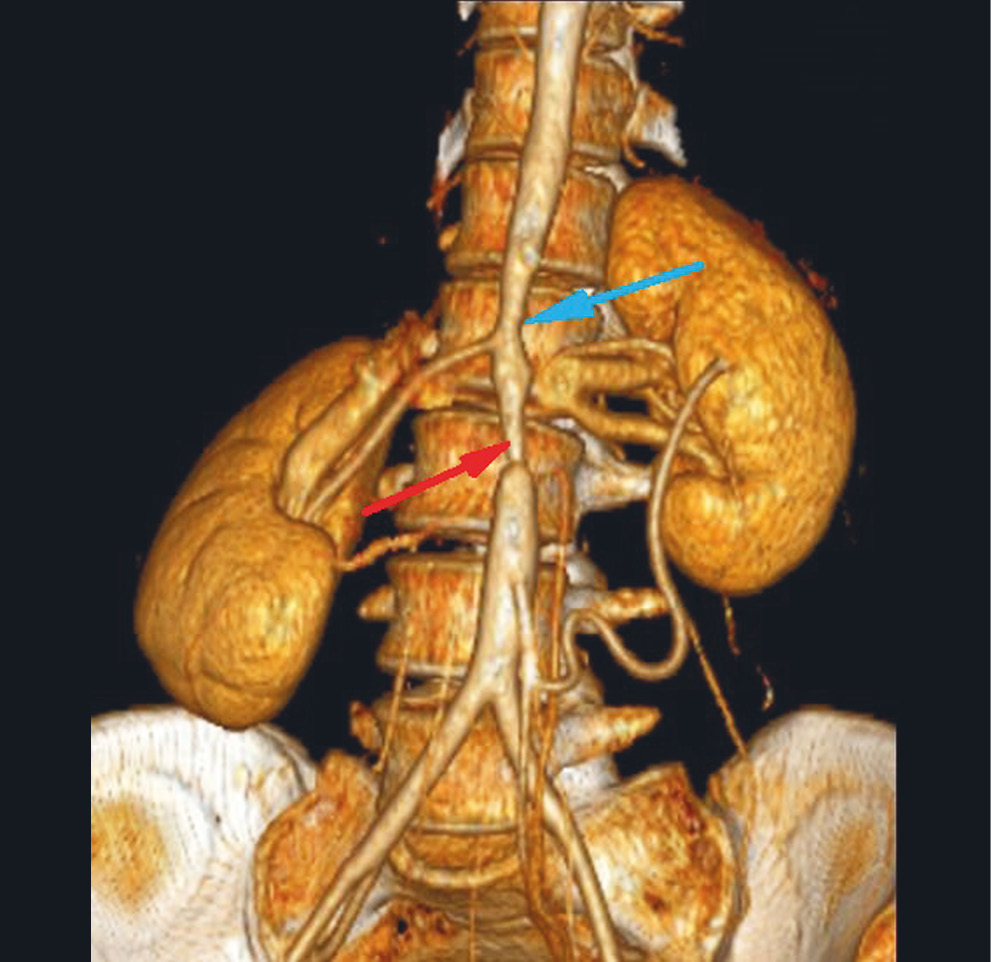

В ноябре 2010 г. в отделении кардиохирургии Донецкого клинического территориального медицинского объединения (ДОКТМО) было проведено оперативное вмешательство в объеме стентирования брюшного отдела аорты, бифуркационного стентирования почечных артерий слева (рис. 2, 3).

Рис. 2. Та же пациентка: мультисрезовая компьютерная томография грудного и брюшного отделов аорты (3D-реконструкция) после оперативного вмешательства

Примечание. Красная стрелка — стент брюшного отдела аорты; синяя стрелка — стент в почечной артерии.